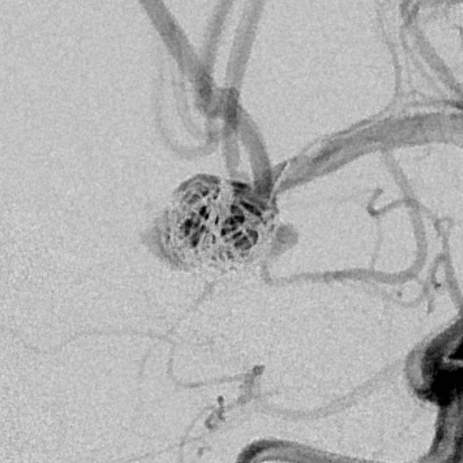

粗大分支从破裂瘤体上发出来,急性期能单纯致密栓塞吗?

最终,动脉瘤瘤体致密栓塞,各个分支保留良好